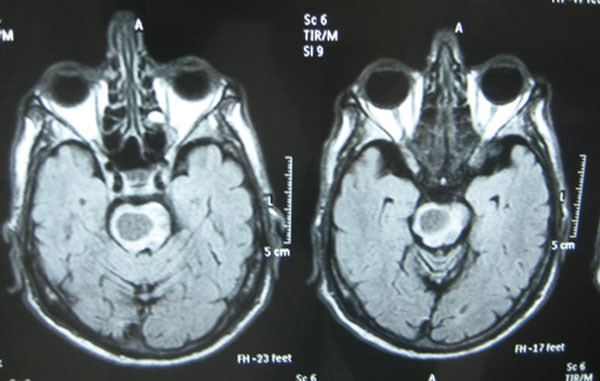

Un nuevo estudio de imágenes mantiene el diagnóstico previo. Los cortes de la tomografía computada se extendieron esta vez a zona del cráneo, y el radiólogo informa como hallazgo una lesión solitaria a nivel de la protuberancia. Se solicita estudio de resonancia nuclear magnética (RNM) (Fig. 3) que muestra absceso protuberancial no piogénico y flegmón maxilar izquierdo con colección parasinfisiaria izquierda.

La última RNM concluye que lesiones cerebrales son metastásicas.

Figura 3

Muestra absceso protuberancial no piogénico